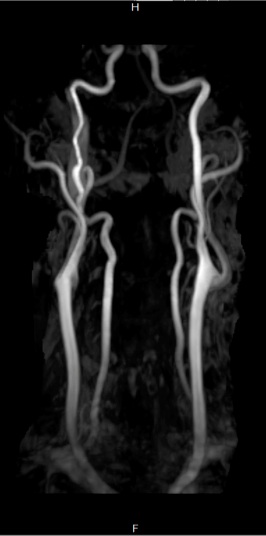

Case Presentation: A 46 year-old man with a past medical history of untreated hypertension presented with right ptosis and miosis. The patient was in his usual state of health until one month prior to presentation, when he developed right retrobulbar pain in the absence of additional upper airway or constitutional symptoms. The patient subsequently noticed right eyelid droop and right periorbital swelling. During an aerobic exercise session, the patient noticed hyperemia and perspiration limited to the left half of his face; he took a self-portrait using his cellphone camera. The patient immediately presented to his primary medical doctor’s office, where his blood pressure was over 200/100 mmHg. He was referred to the Emergency Department. Physical exam revealed right eye ptosis and miosis, and the patient’s self-portrait confirmed anhidrosis, consistent with Horner syndrome. The patient’s blood pressure was 211/176 mmHg; physical and neurologic exams were otherwise normal. He has no family history of connective tissue disease. MRI and MRA of the brain, head, and neck revealed right internal carotid artery dissection without evidence of ischemia or infarction. He was admitted to the hospital. Blood pressure was controlled with oral anti-hypertensives. Aspirin therapy and high-intensity statin were initiated. The patient was discharged home with neurologic and vascular surgical follow-up appointments.